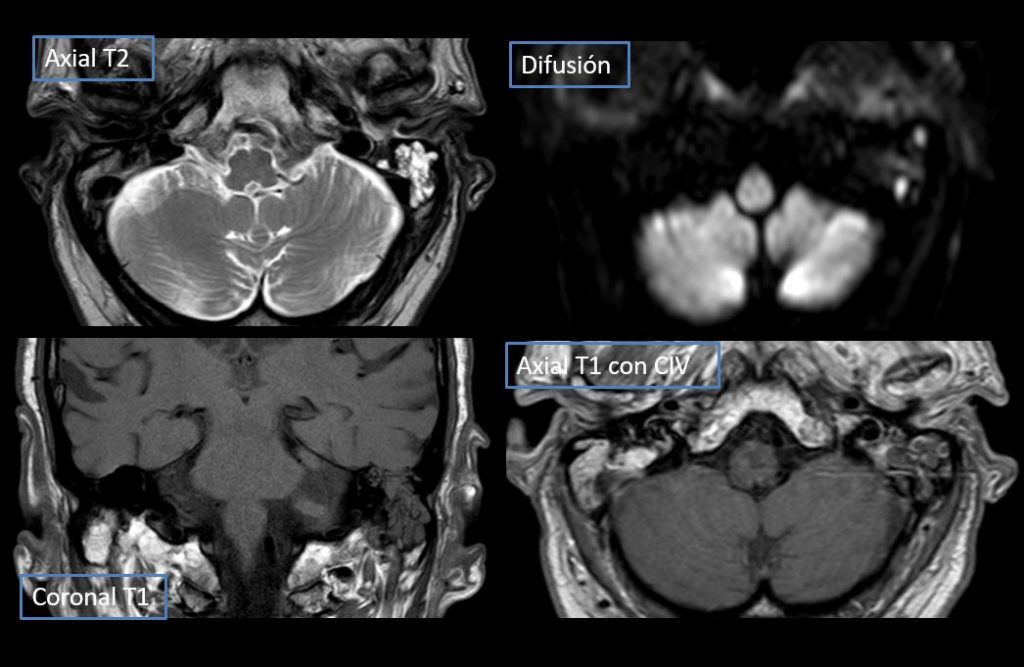

FIGURA 2 (RM)  a) Ocupación completa oído medio izdo por material hipo T1 e hiper T2 que no realza tras la administración de contraste b) Absceso subperióstico c) Ocupación completa de oído medio izquierdo por material hipo T1 e hiper T2 (en difusión muestra pequeños focos de restricción y tras administración de contraste áreas de realce).